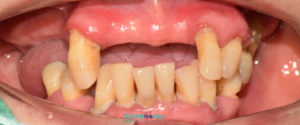

환자분께서는 다수의 치아 상실로 인해

그동안 식사나 대화 시 불편함이 많아

사람을 만나는 일조차 망설여질

정도였다고 말씀하셨는데요.

치료가 마무리된 후에는

양쪽으로 음식물을 저작하는 데

편안함을 느끼셨고,

웃는 모습도 훨씬 자연스러워졌다고

하시며 매우 만족해하셨습니다.